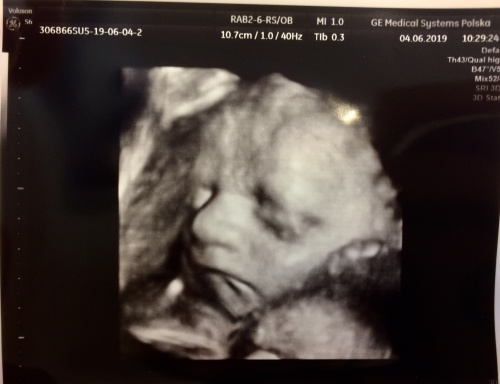

Drzewko Pomarańczowe - fajnie że wszystko po usg dobrze i synuś zdrowiutki:)Jak macie jakies fotki 3D to wrzucajcie, miło popatzreeć na takie słodkie, dziecięce buźki. Mój ostatnio wcale nie chciał podować, tylko jak zwykle jajka z siusiakiem pokazał

Agagusia wrote:Jak macie jakies fotki 3D to wrzucajcie, miło popatzreeć na takie słodkie, dziecięce buźki. Mój ostatnio wcale nie chciał podować, tylko jak zwykle jajka z siusiakiem pokazał

Hehe, my byliśmy wczoraj i nasz mały też tylko pięknie pokazał jajka z siusiakiem, a buźki nie chciał

więc nie mamy ładnej fotki z buźka.

My dziś po standardowej kontroli. Dziś w końcu Tytek pokazał buzię